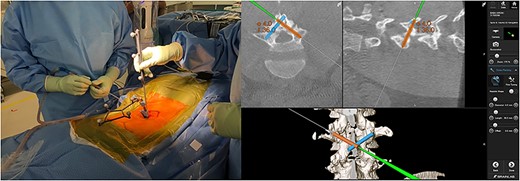

Skin incisions for screw insertion were made bilaterally (each 10 mm in length). The fascia and paravertebral muscles were cut for screw insertion. The screw insertion point, insertion angle, and screw length were planned using the navigation pointer and were registered in the navigation system (Fig. 2). The robotic arm was moved manually to a position near the target point, and it then automatically moved to the planned point precisely. The canula was inserted though the robotic arm, and the screw trajectory was made using a power drill (Fig. 3). After drilling, the guidewire was inserted into the drilled hole and tapping was performed through the guidewire. Finally, the planned screws were inserted via the guidewire. The screw position was confirmed by fluoroscopy and postoperative X-ray. Each wound was washed and closed without a drain tube (Fig. 4). There were no intraoperative complications.

Screw planning; the appropriate screw length and angle were displayed on navigation monitor (right panel).